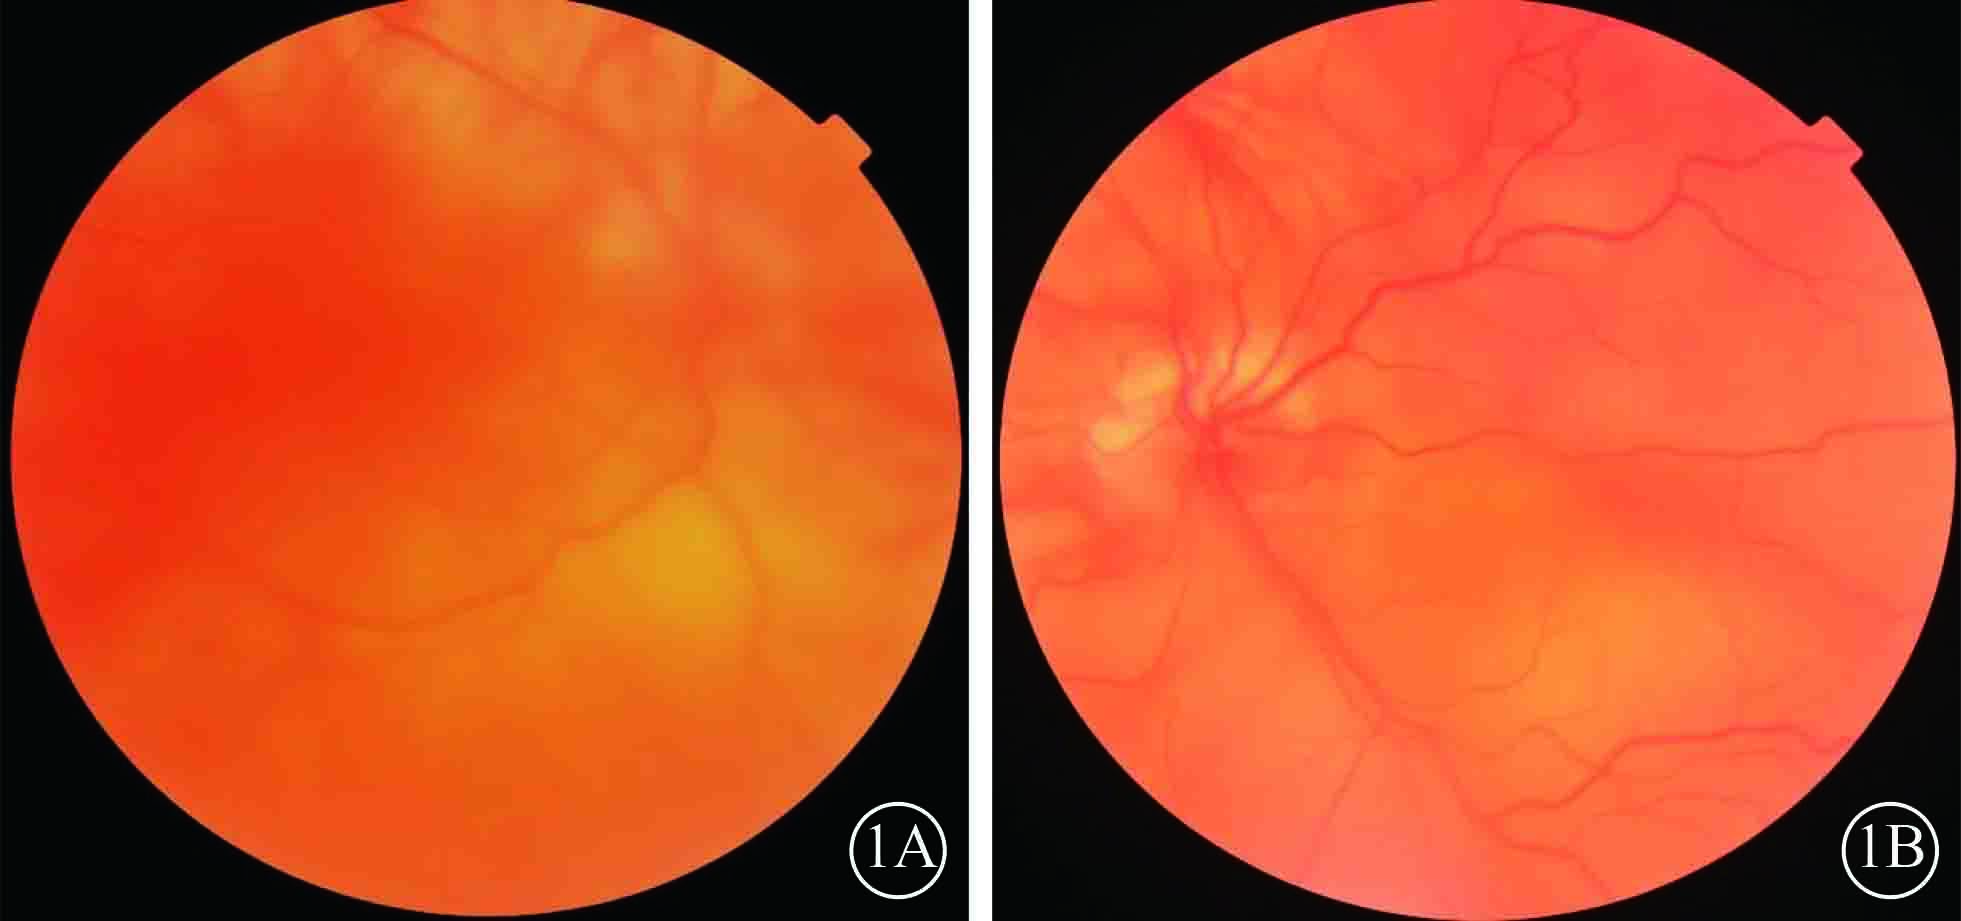

圖1

雙眼手術前彩色眼底像。1A. 右眼;1B. 左眼。眼底無色素,視網膜廣泛脫離

圖1

雙眼手術前彩色眼底像。1A. 右眼;1B. 左眼。眼底無色素,視網膜廣泛脫離

患者男,35歲。因體檢發現雙眼視網膜脫離1月余于2015年3月12日來我院眼科就診。患者自幼皮膚、毛發、虹膜無色素;雙眼視力差、畏光。否認外傷史、家族史。眼部檢查:右眼視力數指/30 cm,左眼視力0.1;雙眼矯正視力均無提高。雙眼眼瞼皮膚及睫毛均無色素;眼球水平震顫;角膜透明,瞳孔圓,虹膜半透明;晶狀體透明。雙眼眼底呈橙色。右眼全視網膜脫離,左眼0~8點時鐘位視網膜脫離(圖1);雙眼視網膜裂孔均窺不清。A型超聲檢查,右眼、左眼眼軸長度分別為26、28 mm。診斷:(1)雙眼孔源性視網膜脫離(疑似);(2)雙眼高度近視;(3)眼皮膚白化病。分別于2015年3月23日、5月11日行左眼、右眼視網膜復位手術。采用標準25G經睫狀體平坦部玻璃體切割手術。手術中見左眼視網膜裂孔分別位于 1、2、4、6點時鐘位,右眼裂孔位于8、11點時鐘位。先采用眼內電凝對裂孔邊緣進行標記,電凝處理后裂孔邊緣呈白色外觀(圖2);視網膜復位后,采用視網膜冷凍替代常規激光光凝對裂孔進行封閉;最后進行硅油眼內填充。雙眼均于手術后3個月行硅油取出手術。硅油取出后3個月,雙眼視網膜復位良好,眼底呈橙色,透見脈絡膜大血管(圖3);6個月,右眼視網膜復位良好,左眼下方視網膜再次脫離。于2016年2月1日再次行左眼視網膜復位手術、硅油填充。2016年12月27日隨訪,右眼視網膜復位良好;左眼硅油填充,下方視網膜仍有局部脫離(圖4)。

患者男,35歲。因體檢發現雙眼視網膜脫離1月余于2015年3月12日來我院眼科就診。患者自幼皮膚、毛發、虹膜無色素;雙眼視力差、畏光。否認外傷史、家族史。眼部檢查:右眼視力數指/30 cm,左眼視力0.1;雙眼矯正視力均無提高。雙眼眼瞼皮膚及睫毛均無色素;眼球水平震顫;角膜透明,瞳孔圓,虹膜半透明;晶狀體透明。雙眼眼底呈橙色。右眼全視網膜脫離,左眼0~8點時鐘位視網膜脫離(圖1);雙眼視網膜裂孔均窺不清。A型超聲檢查,右眼、左眼眼軸長度分別為26、28 mm。診斷:(1)雙眼孔源性視網膜脫離(疑似);(2)雙眼高度近視;(3)眼皮膚白化病。分別于2015年3月23日、5月11日行左眼、右眼視網膜復位手術。采用標準25G經睫狀體平坦部玻璃體切割手術。手術中見左眼視網膜裂孔分別位于 1、2、4、6點時鐘位,右眼裂孔位于8、11點時鐘位。先采用眼內電凝對裂孔邊緣進行標記,電凝處理后裂孔邊緣呈白色外觀(圖2);視網膜復位后,采用視網膜冷凍替代常規激光光凝對裂孔進行封閉;最后進行硅油眼內填充。雙眼均于手術后3個月行硅油取出手術。硅油取出后3個月,雙眼視網膜復位良好,眼底呈橙色,透見脈絡膜大血管(圖3);6個月,右眼視網膜復位良好,左眼下方視網膜再次脫離。于2016年2月1日再次行左眼視網膜復位手術、硅油填充。2016年12月27日隨訪,右眼視網膜復位良好;左眼硅油填充,下方視網膜仍有局部脫離(圖4)。

圖1

雙眼手術前彩色眼底像。1A. 右眼;1B. 左眼。眼底無色素,視網膜廣泛脫離

圖1

雙眼手術前彩色眼底像。1A. 右眼;1B. 左眼。眼底無色素,視網膜廣泛脫離